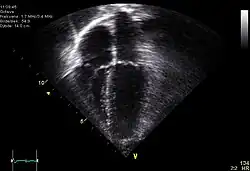

| Diagnostic method | ECG, chest x-ray, bedside echocardiogram |

Diagnosis of traumatic cardiac arrest is initially made with electrocardiogram with EMS or in the emergency department. Clinicians will also order diagnostic testing that may include chest x-ray, bedside ultrasound and echocardiogram, and blood gas levels. A type and cross will be ordered to match the patient to receive blood transfusion if necessary.

Other work-up involved in diagnosis of a trauma patient may include e-FAST, RUSH exam, CBC, pelvic X-ray, and CT of the head, neck, chest, abdomen, and pelvis.